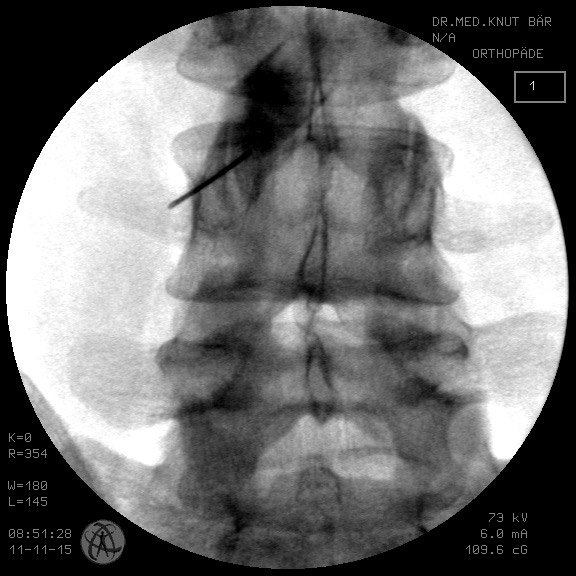

In unserer Praxis wird die operationsersetzende Technik der Nervenwurzelumspülung (MISS minimal invasive spine surgery) beim Bandscheibenvorfall, der spinalen Stenose und bei Gleitwirbelsituation seit 2006 mit großem Erfolg zur Anwendung gebracht und kann fast immer einen operativen Eingriff vermeiden helfen (Abbildung 5, Abbildung 6).

Abb. 5, 6: Gewebeschonende minimalinvasive Therapie an der Wirbelsäule unter Sicht